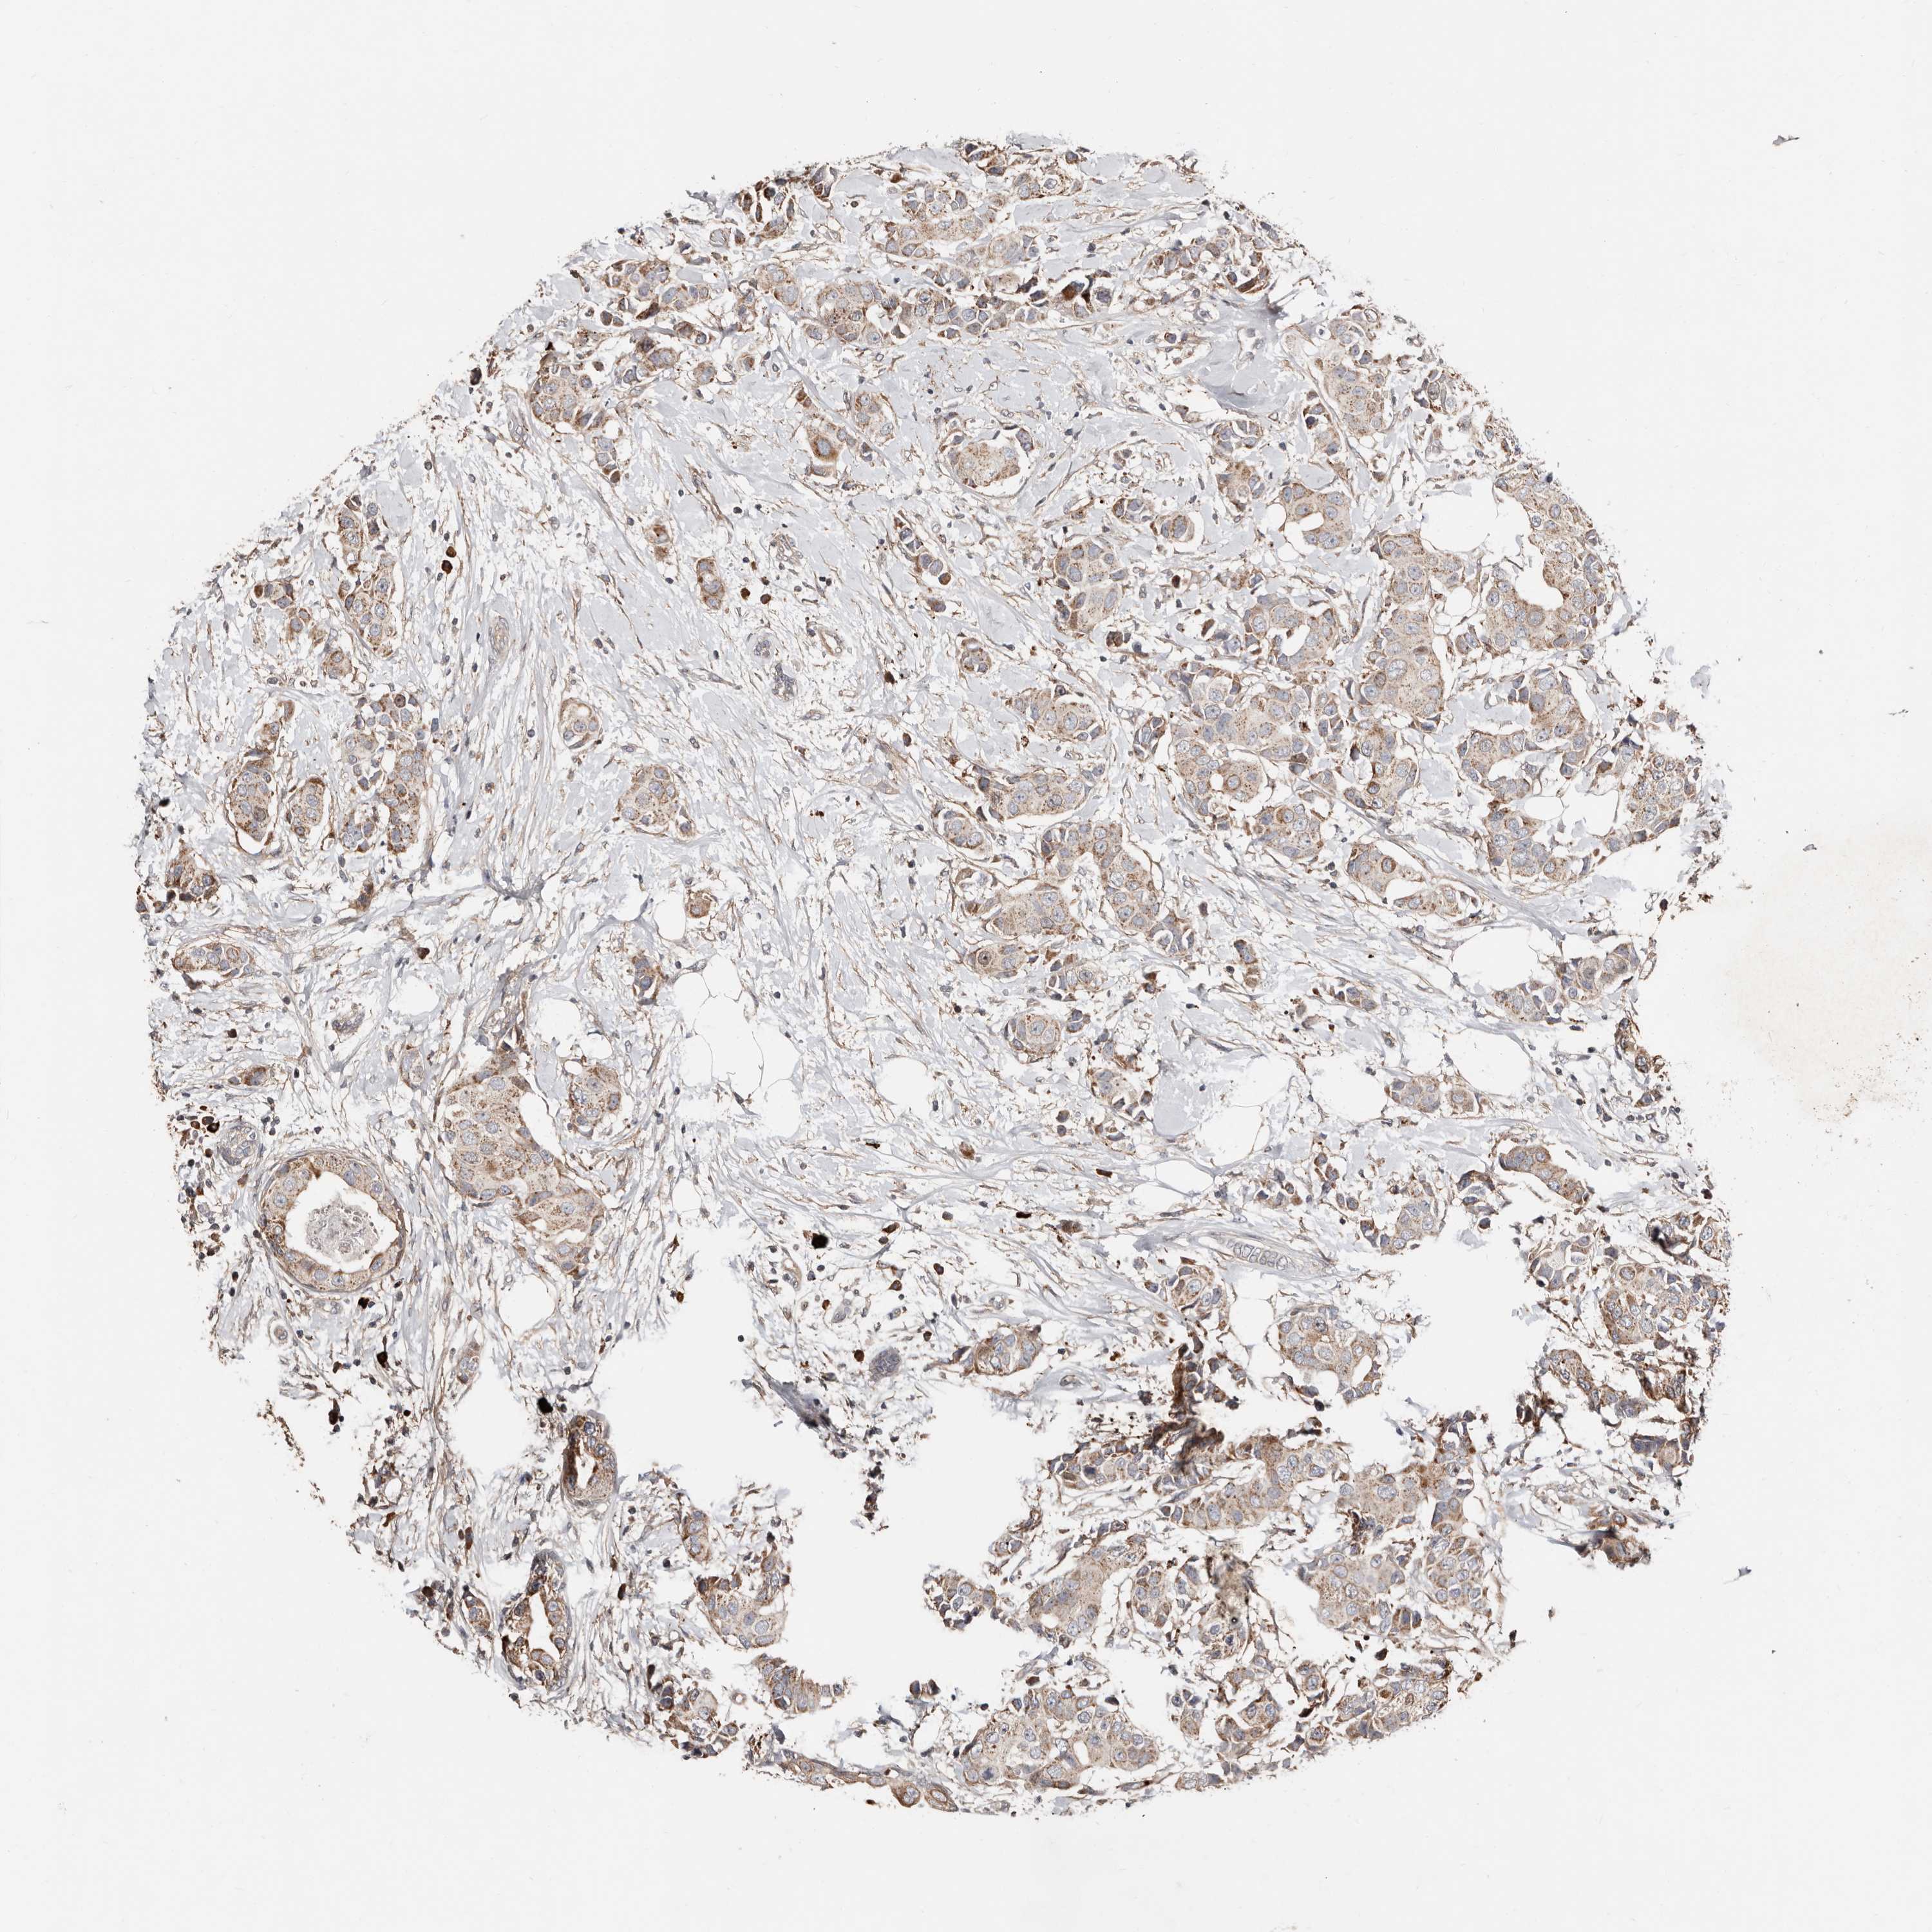

BRCA TCGA BRCA VALIDATION PROTEIN EXPRESSION

Breast cancer

Human cancer